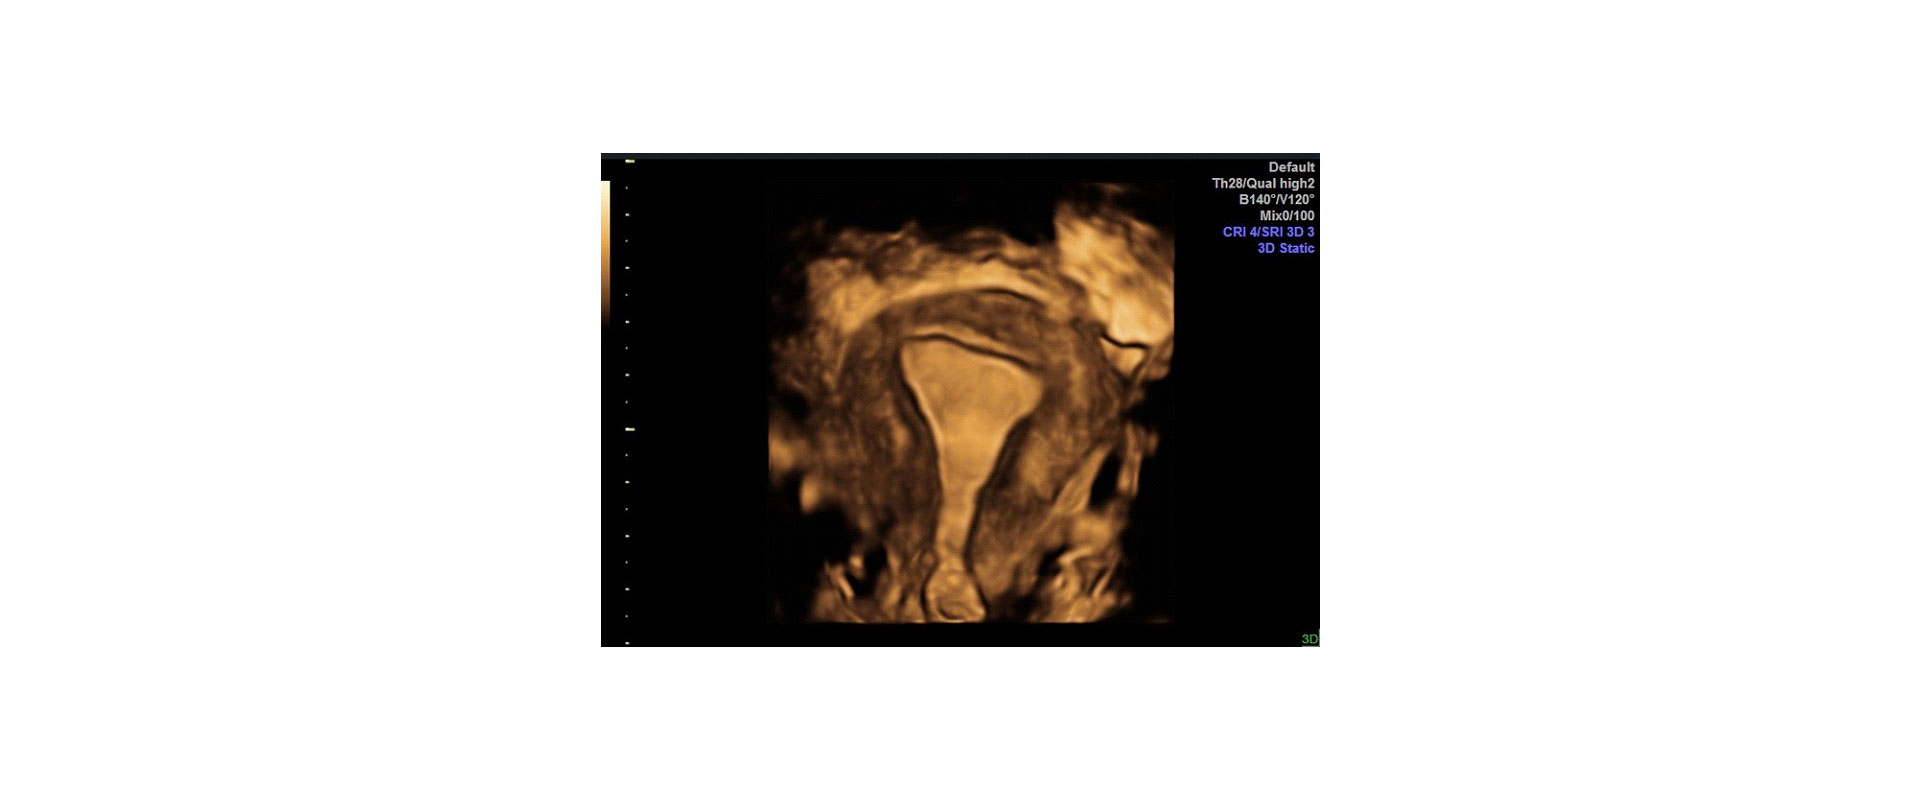

⦁ και τη φυσιολογική ανατομία της μήτρας και πιθανή παθολογία της

Στο ιατρείο μας χρησιμοποιούμε μηχάνημα υπερήχων τελευταίας τεχνολογίας έτσι ώστε να έχουμε ακίνητη τρισδιάστατη απεικόνιση του εμβρύου (3D) και της μήτρας ή να βλέπουμε το έμβρυο τρισδιάστατο όπως κινείται σε πραγματικό χρόνο – real time (4D).

✓ Ακριβής Διάγνωση: Εξαιρετική ευκρίνεια εικόνων για τη διάγνωση γυναικολογικών προβλημάτων.

✓Εκτίμηση Ανατομίας: Βελτιωμένη ανάλυση της ανατομίας των γυναικείων αναπαραγωγικών οργάνων.

⦁ Στη γυναικολογία πραγματοποιείται οποιαδήποτε στιγμή